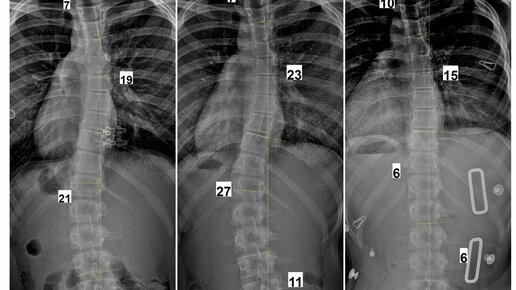

II степень по Чаклину – 11-30 градусов. Это пограничная стадия, когда решается, требуется корсет для лечения сколиоза или нет.